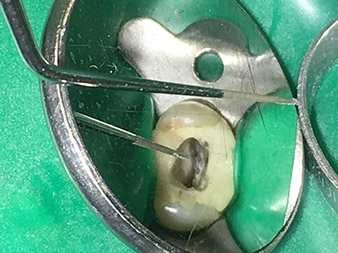

4E tip

Atraumatic preparation of the cavity floor with the 4E tip.

The 4E tip – this instrument is optimally suited to preparation of the cavity floor at the transition to the canals. It can be used to round off the transition between the canal and the cavity floor optimally so as to produce a funnel leading into the canal. In addition, the instrument is the ideal choice for removing dentine overhangs from canals.

All in all, the cavity can be prepared very efficiently and minimally invasively with this tip by optimally rounding off and smoothing overhangs, corners and edges.